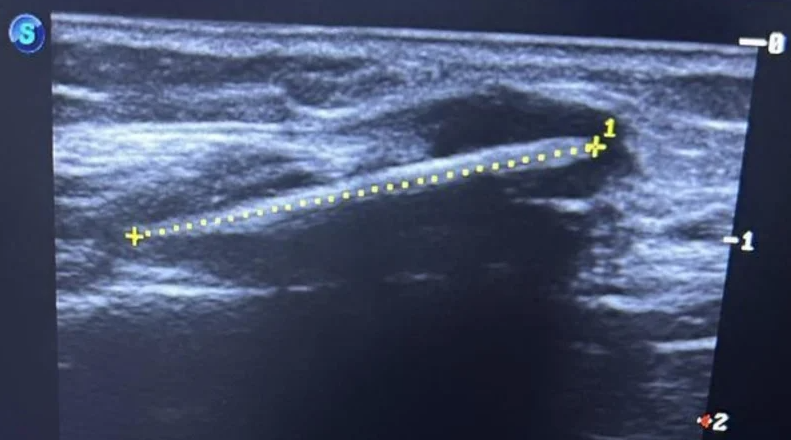

內媒報道,姓李女事主時常感到腳痺,步行時又覺疼痛。她早前在長沙市第三骨科醫院求診,醫生觸診時,很快便在她小腿中下段外側摸到硬塊,隨即安排她照X光。

結果發現,女事主的右腓骨外側軟組織內有條狀異物,醫生估計是異物殘留,進一步向女事主問診後,得知原來她16年前在屋外玩耍時,曾被竹籤刺中右腿,但當時傷口很小,而且沒有明顯流血,家人即不以為意。